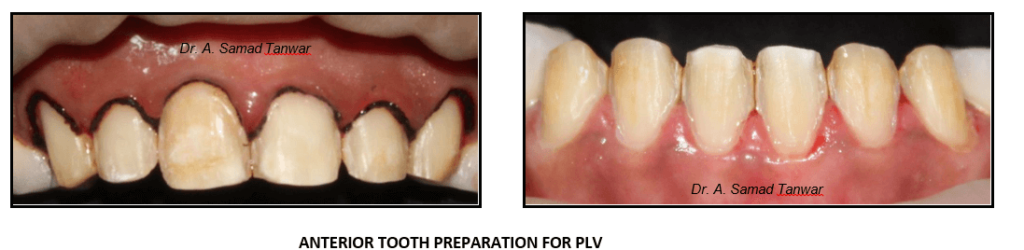

Gingival retraction was done using 000 knitted retraction cord

Double mix double step impressions were made using PVS elastomeric impression material

After the preparation stump shade selection was done using VITA stump shade guide.